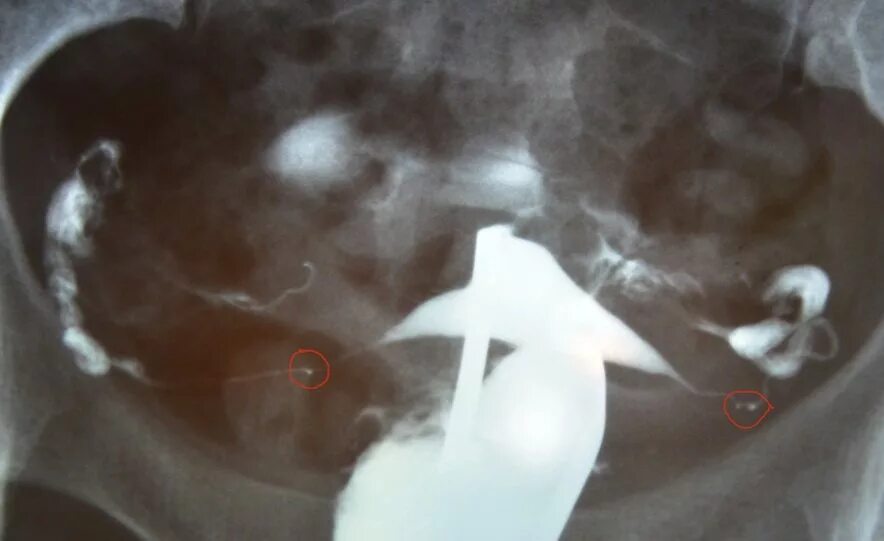

Проходимость маточных труб форум